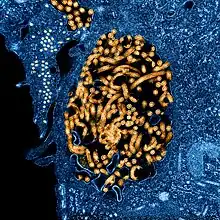

.jpg)

La fusion de l'enveloppe du virion avec la membrane plasmique de la cellule hôte a pour effet de libérer la capside nucléaire dans le cytoplasme de la cellule cible. L'ARN polymérase ARN-dépendante L dénude partiellement l'ARN génomique et le transcrit en ARN messager à polarité positive qui sont ensuite traduits en protéines. L'ARN polymérase L du virus Ebola se lie à un promoteur unique situé à l'extrémité 5' du génome viral. L'expression des gènes se déroule ensuite séquentiellement, avec une probabilité croissante de s'interrompre à mesure que la polymérase progresse le long du brin d'ARN génomique à transcrire : le premier gène à partir du promoteur est ainsi davantage exprimé que le dernier gène à l'extrémité 3'. L'ordre des gènes sur le génome viral offre ainsi un moyen simple, mais efficace de réguler leur transcription : la nucléoprotéine NP, codée par le premier gène, est produite en plus grande quantité que la polymérase L, codée par le dernier gène. La concentration de cette nucléoprotéine dans le cytosol de l'hôte détermine le moment où la polymérase L bascule de la transcription — production d'ARN messager à partir de l'ARN génomique — vers la réplication virale — production d'antigénomes d'ARN à polarité positive par réplication intégrale d'un ARN génomique original. Ces antigénomes sont à leur tour transcrits en génomes viraux d'ARN à polarité négative qui interagissent avec les protéines structurelles préalablement traduites à partir de l'ARN viral. Des particules virales s'auto-assemblent à partir des protéines et du matériel génétique nouvellement produits à proximité de la membrane cellulaire. Elles bourgeonnent hors de la cellule en se recouvrant d'une enveloppe virale issue de la membrane plasmique, où s'insèrent les glycoprotéines GP, ce qui libère de nouveaux virions prêts à infecter d'autres cellules[29].